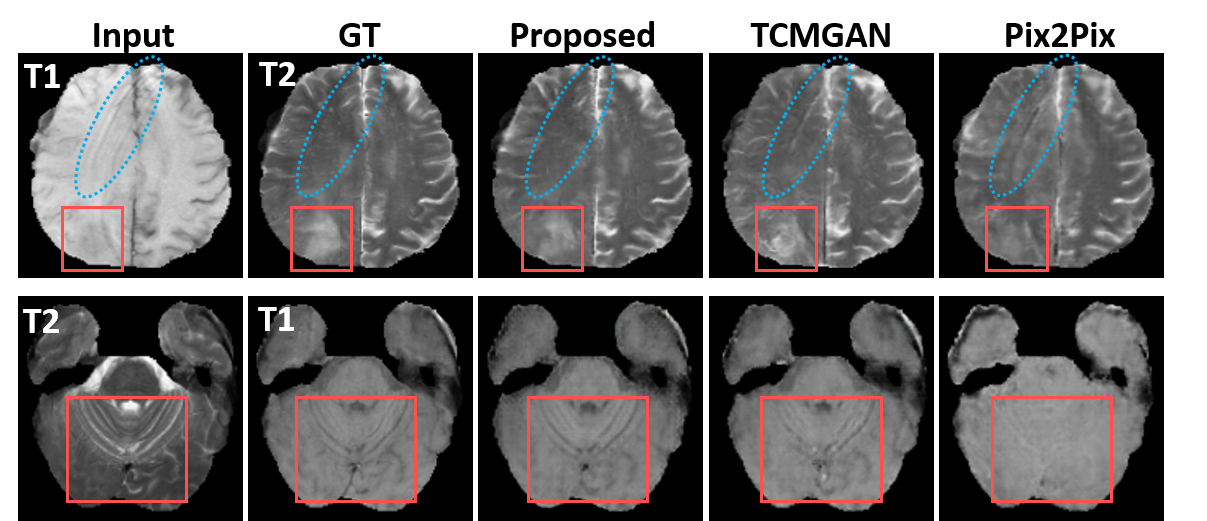

Refer to caption

Fig. 3: Comparison of different methods for the T1-weighted and T2-weighted MR translation. GT indicates the ground truth xysubscript𝑥𝑦x_{y}.

The qualitative comparisons with the 1-to-1 translator Pix2Pix [6] and 1-to-3 translator [10] are shown in Fig. 3 along with our proposed framework. The proposed framework was able to generate visually pleasing results with better shape and structure consistency when visually assessed. From the red box in the first row, we can see that the tumor area was better maintained with the help of the cycle-constraint compared with [10] which uses the additional tumor-consistent loss. Also, the artifact shown in the T1-weighted MR image (i.e., stripes indicated by the blue circle) yielded similar stripes as shown in the T2-weighted MR image with TCMGAN and Pix2Pix. Our disentangled encoder was able to eliminate the artifact and enforce the latent representation following the distribution of normal MR images.